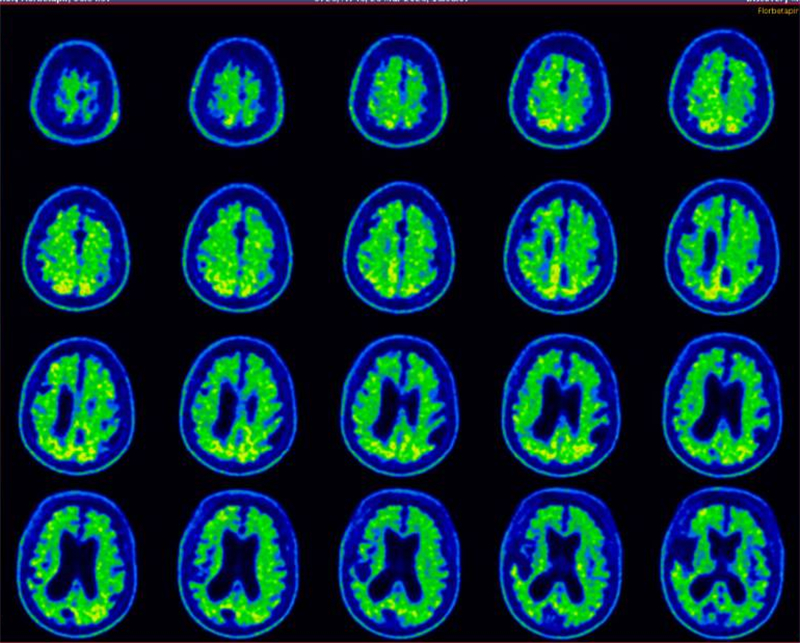

经过PET-CT影像学评估、脑脊液生物标志物检测及多学科会诊,医院高级认知障碍诊疗中心团队确认患者虽属重度阿尔茨海默病,但无严重基础疾病,符合手术指征。